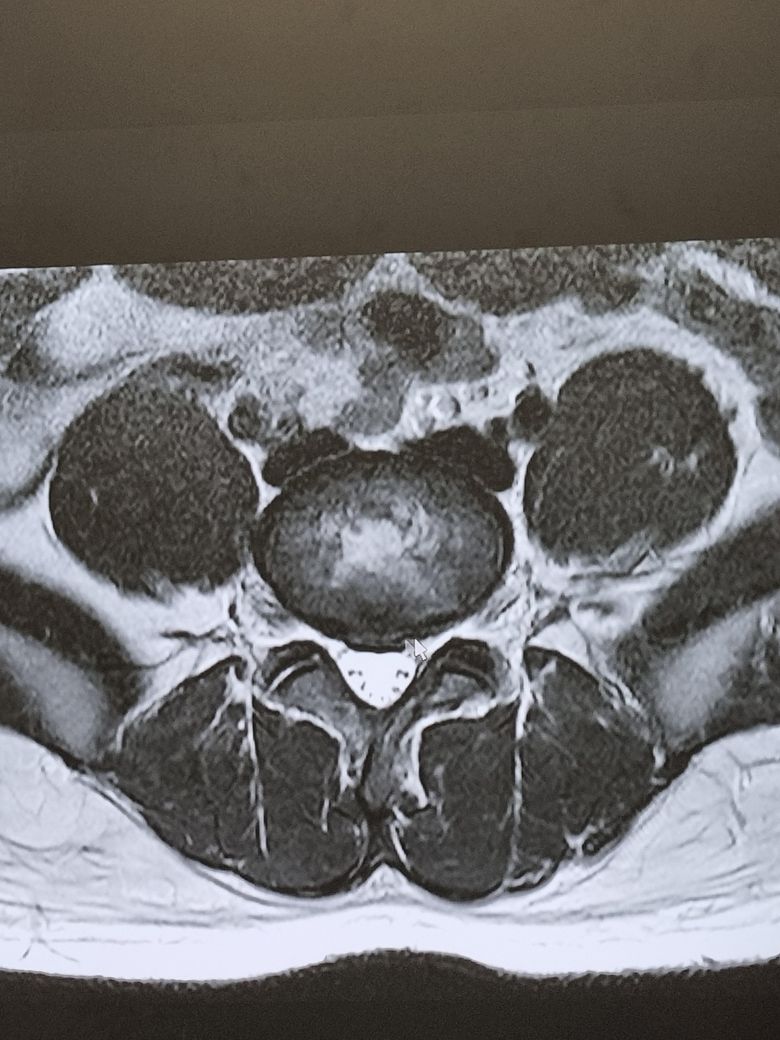

사진으로 디스크가 심한지 구분해주실분 구합니다.

다리 방사통이 있어서 병원에서 mri촬영을하고 염증 가라 앉하는 주사 맞고 계속 3개월간 주사치료해야한다는데 혹시 사진으로 보았을때 심한상태인가여 아니면 자연치유가 가능할까요 제발 알려주세요 부탁드립니다

사진상을 볼때에는 크게 심해보이지는않는데요 운동과 스트레칭을 꾸준하게하면서 관리하면 괜찮을 정도인거같습니다

MRI 사진을 보면 디스크가 신경을 누르고 있는 정도에 따라 심각도가 달라지며 이는 전문의의 정밀 판독이 필요합니다. 다리 방사통이 있다면 신경 압박은 확실한 상태로 보이고 주사치료나 물리치료로 호전될 수 있는 경우도 많아요 다만 증상이 심하거나 지속되낟면 수술적 치료까지 고려될 수 있으니 두세곳 병원에서 의견을 들어보는 것도 추천드립니다

4,5번 쪽에 디스크가 조금 튀어나온거 같은데, 제가 여러 환자들 본 경우 사진상으로는 그렇게 심해보이진 않습니다 재활 운동하고 잘하는 도수치료 받으시면서 디스크가 더 튀어나오지 않게 잘 관리 해주시면 정상 활동 가능합니다

심하지 않습니다 영상을 전반적으로 다시 봐야 정확한 설명이 되겠지만 우선 지금 보여주신것만 보면 가벼운 디스크 탈출입니다. 요추 5번/천추 1번 사이에 있습니다.

이런 경우에 요추전만 자세만 잘 하고있어도 자연적으로 회복이 됩니다. 방사통이 많이 불편하다면 주사치료를 해서 통증을 줄여놓고 허리를 절대 구부리지 않는 요추전만 자세만 해주시면 충분히 좋아지실 수 있겠습니다.